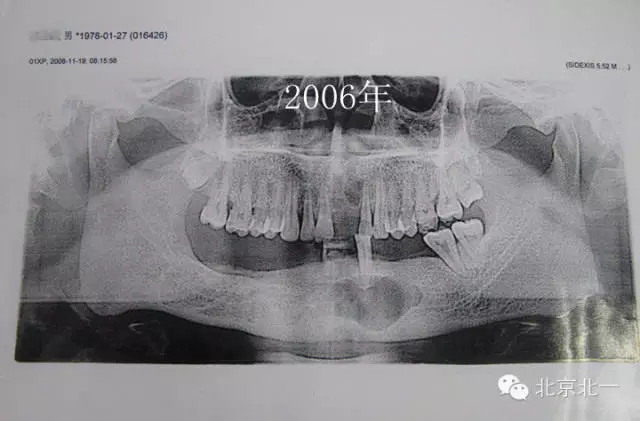

圖2、手術后第一次復發(fā)

640 (2).webp (1).jpg